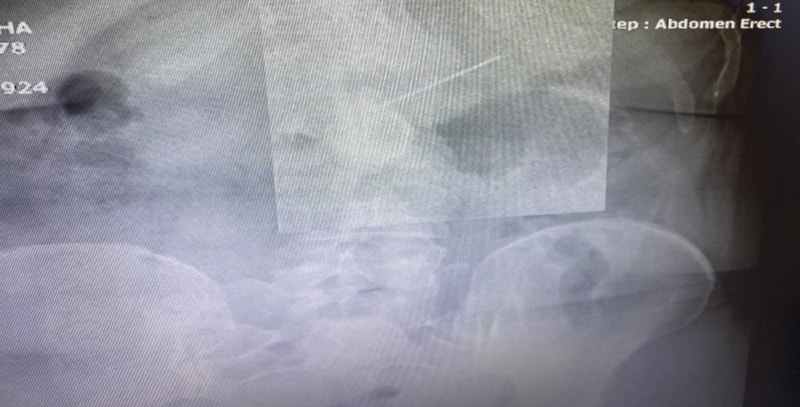

Başakşehir Çam ve Sakura Şehir Hastanesi acil servisinde tedavi altına alınan kadının, hemen film çekildi.

Toplu iğnenin mideye ulaştığı belirlenirken gerçekleştirilen endoskopik işlemle hastanın midesindeki iğne olduğu noktadan alındı.

Biz acil servilerde yaptığımız görüntülemelerde iğnenin henüz daha midede olduğunu, daha fazla ileriyle gitmediğini gördük. Akabinde hastamızı endoskopi ünitemize aldık, burada yaptığımız endoskopide de tam mide çıkışında mide mukozası dediğimiz en iç tabasına saplanmış şekilde gıda artıklarının arasında durduğunu gördük. Zor da olsa özel aletlerimizi kullanarak iğnemizi tuttuk, daha sonra endoskopi kanalının içinden hastamıza herhangi bir zarar vermeden dışarıya çıkarttık. Bu iğnenin hastamıza bu aşamaya kadar herhangi bir zarar vermediğini yemek borusunda, midesinde yırtılma yapmadığını gördük.”